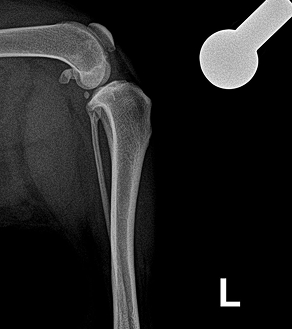

< 정상적인 십자인대 >